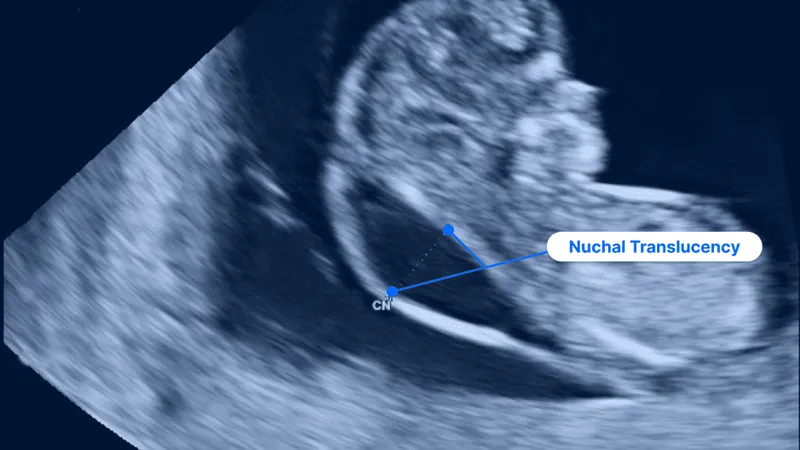

- Ultrasound: Nuchal Translucency (NT). A fluid collection >3.0 mm is a key marker.

- ↑ Nuchal Translucency/Fold: Strongest marker for Trisomy 21. NT >3 mm in 1st trimester.

⭐ While most soft markers are non-specific, a thickened nuchal fold (≥6 mm) in the second trimester is one of the strongest individual markers for Down syndrome.

- Increased nuchal translucency (NT) is a key first-trimester marker for aneuploidies like Trisomy 21.